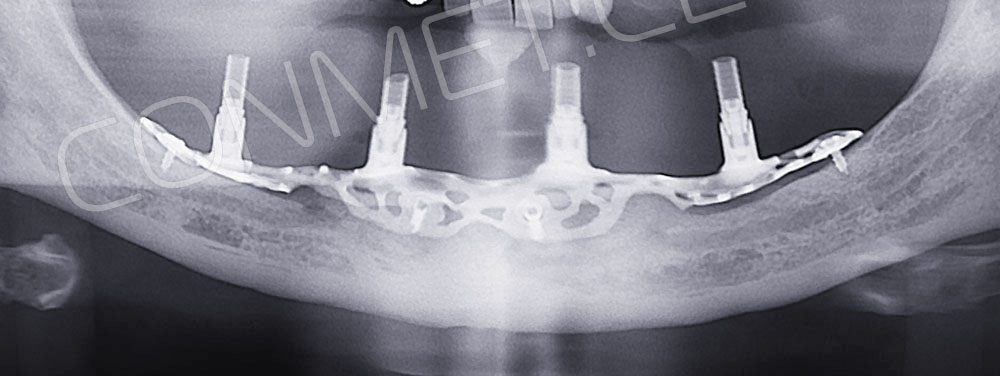

2. После этого произвели компьютерное моделирование самого имплантата и фиксирующих элементов. Примечательно, что в абатментах, использовался отлично зарекомендовавший себя и проверенный десятилетиями интерфейс КОНМЕТ! В результате получили несколько специальных файлов, позволяющих не только сделать сам имлантат, но еще до операции изготовить и сами зубы. Данные файлы передали в изготовление на специальном 3D оборудовании.

Имплантат напечатали из особого, биосовместимого, медицинского титана на предприятии имеющим соответствующую медицинскую лицензию. Толщина имплантата составила 0,8 мм, а вес всего несколько грамм!

Первый вывод к которому мы пришли, это то, что для данных конструкций имплантатов сохранять внутренний интерфейс с шестигранником и конусом Морзе нецелесообразно из-за ограничения возможностей современной 3D печати титана. Кроме того, техническая обработка после 3D печати такого интерфейса представляет значительные трудности и ведет к неоправданному увеличению цены. Поэтому пришли к единодушному мнению, что лучший вариант-это опорные элементы полностью повторяющие абатменты-мультиюниты.

Клинические работы с субпериостальными имплантатами производства Конмет, проведенные в 2019 году, позволили унифицировать интерфейс данных имплантатов под современный цифровой протокол. Более того, необходимые конструкционные элементы были введены в официальную базу под программу Exocad. Что позволило сократить время изготовления зубного протеза до 1-3 дней!